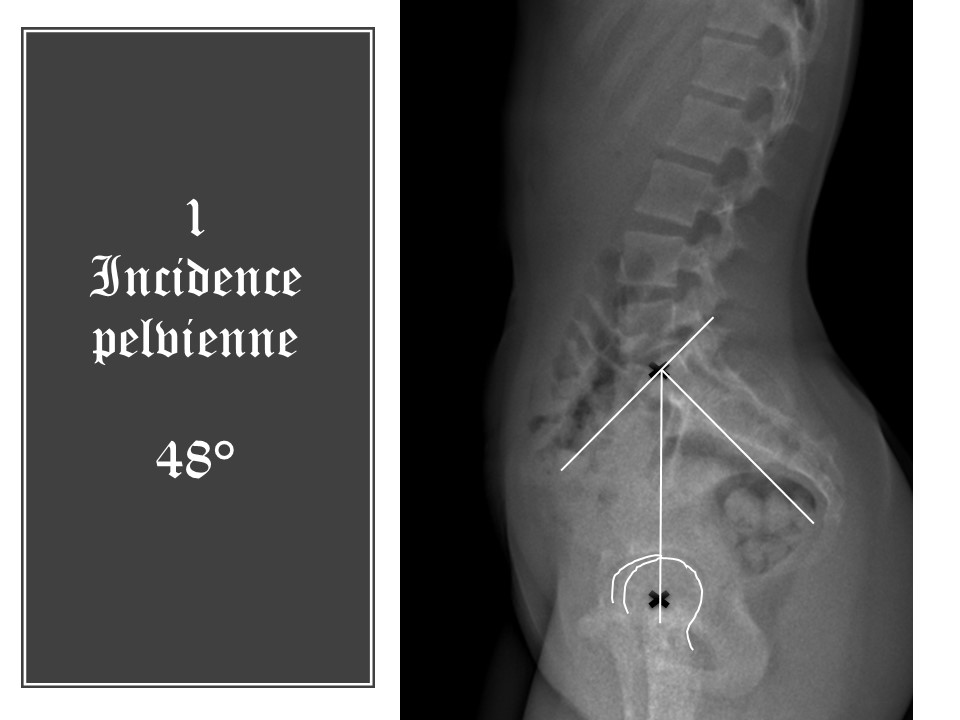

Nous procéderons de bas en haut. Tout d'abord, il faut déterminer le centre des têtes fémorales. Si la superposition n'est pas parfaite, nous choisirons une moyenne entre les deux centres. Le deuxième point est le milieu du plateau supérieur de S1. L'incidence pelvienne est l'angle formé par la perpendiculaire au plateau sacré en son centre et la ligne joignant le centre des têtes fémorales. Elle est ici de 48°.

Cet angle est invariable quelle que soit la position du bassin dans le plan sagittal. En antéversion, la pente sacrée et la lordose s’accentuent

En rétroversion, pente sacrée et lordose diminuent, mais l’incidence lombo-pelvienne reste identique